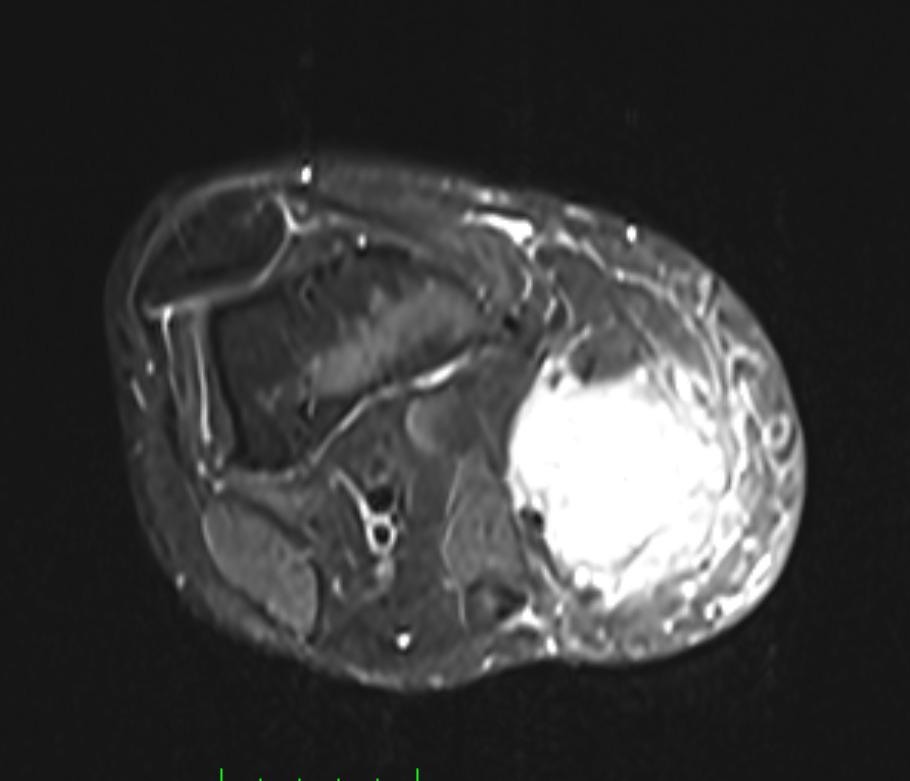

Muscle Cancer